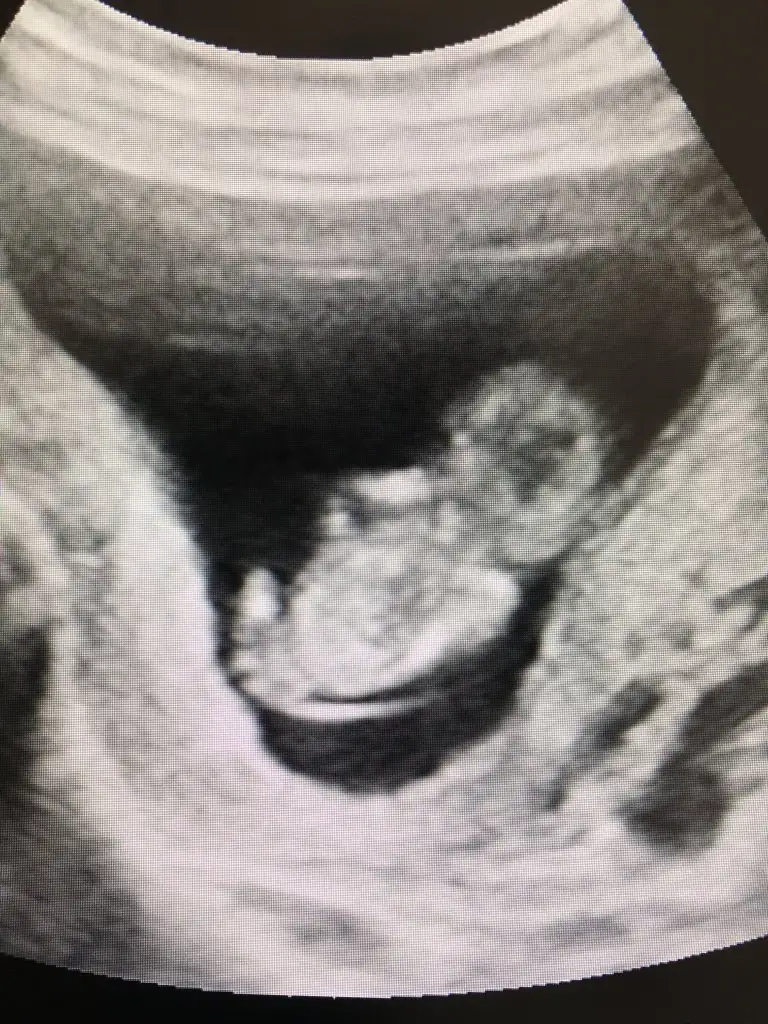

AA evet rengi net olunca çıkıntısı varEki Görüntüle 2895899 Eki Görüntüle 2895900 Az önce instagram üzerinden ücretli bakan birine attım bu şekilde geri dönüş yaptı sizce haklı mı?

Değişme ihtimali var mı peki? Yoksa kesin mi? 11+3 çıktı ama 12+0AA evet rengi net olunca çıkıntısı var![]()

Allah bilir canım erkek görünüyorDeğişme ihtimali var mı peki? Yoksa kesin mi? 11+3 çıktı ama 12+0